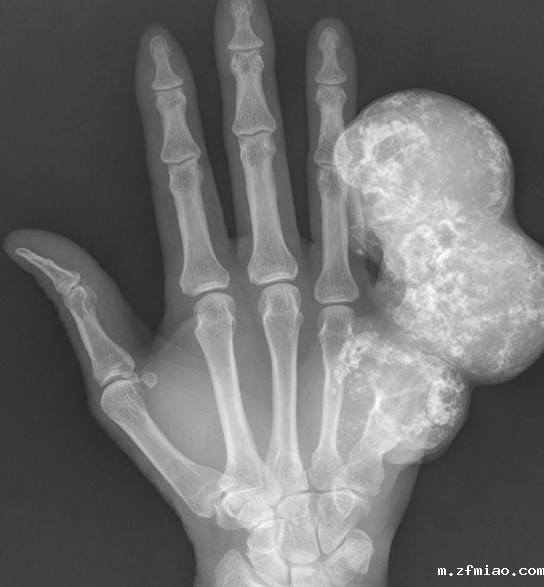

骨密度检测仪器提醒软骨内瘤是一种发生在骨中的良性骨肿瘤。它通常没有症状,或伴有轻度疼痛和无痛肿胀,看起来更像肢体局部肿胀,生长缓慢,多年来体积没有明显变化。目前手术后,黄先生的左手恢复良好。